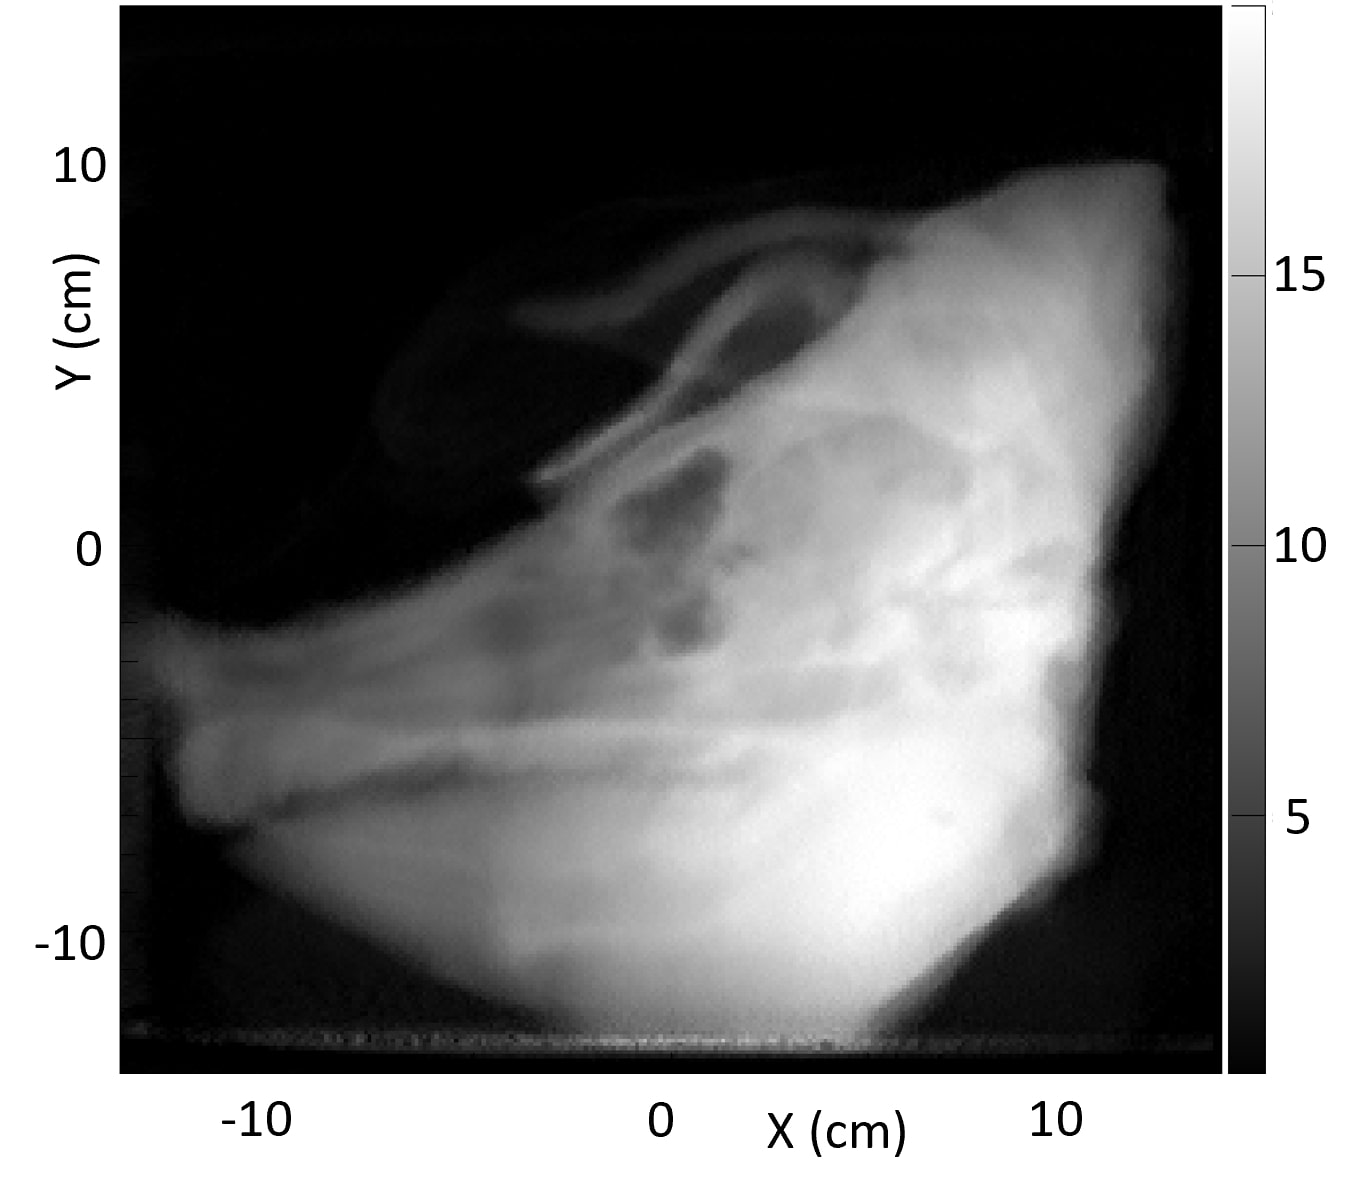

Fig. 8 shows a comparison of the average of ten 1 mm sagittal slices from a lateral region of the pig’s head for pCT and the vertical x-ray CT, in order to reduce noise. Features are slightly blurred due to their change in shape with depth. The grey scale reflects the measured RSP, whereas in Fig. 6 and 7 the grey scales were windowed and levelled to optimize contouring. The largest differences are in regions of heterogeneity such as the teeth and tympanic bullae.

The difference map also clearly shows the systematic discrepancy in the skull and the mandible, while soft tissue regions such as brain and muscle regions show closer agreement. The difference in the tip of the snout is caused by an incomplete set of pCT data through that area. The pencil beam scans used for the pCT data set only covered a cm2 area, so the tip of the snout was not quite covered at lateral angles.